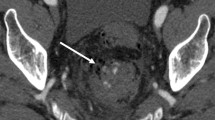

Primary epiploic appendagitis results from torsion of epiploic appendages, leading to ischemic infarction and commonly appears as oval fat-density lesion abutting the colonic wall surrounded by inflammatory changes [33]. From our observations, there is little to no iodine uptake by the hyperattenuating rim or the inner fat density, representing an infarcted appendage, on IOIs, compared to mild increase in iodine uptake in the surrounding inflamed fat (Fig. 2).

A 59-year-old female with left lower quadrant pain (a) contrast-enhanced Axial CT images demonstrate the classic appearance of epiploic appendagitis as a fat-density lesion with a thin rim and surrounding fat stranding, (b) axial IOI demonstrates higher iodine uptake of the surrounding fat secondary to inflammation and lack of iodine uptake within the infarcted epiploic appendage